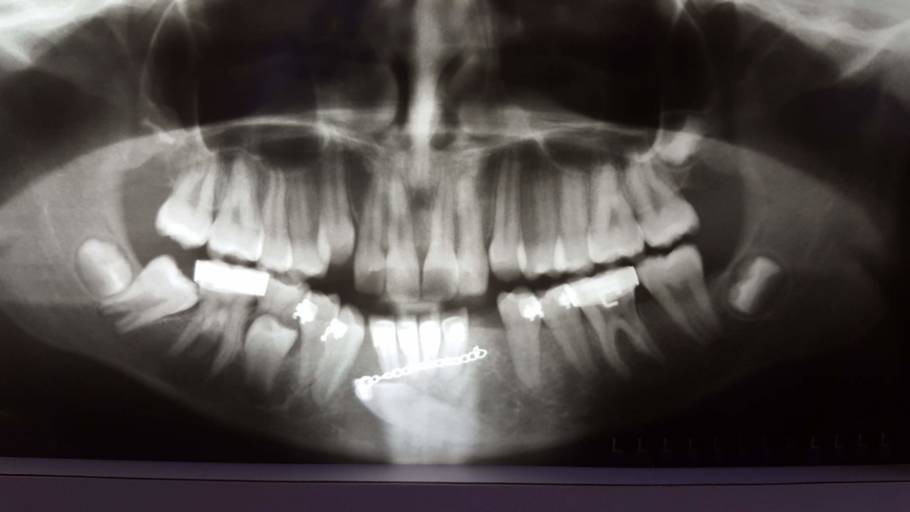

I have an underbite and was wondering if I need surgery

So I’ve had an underbite since I was 10, my orthodontist made me wear braces for 3 years and it didn’t change the bite so he said surgery is only option. Is that true? I don’t want to get surgery nor can I afford it. Is their any other minor surgery or thing that can help change my underbite

Unfortunately, if you have already worn braces for 3 years and your underbite was not corrected, surgery is your only option. Surgery today has a much quicker healing time and has advanced quite a bit over the years. It is best to have the surgery when you are young, as healing is quicker as well. However, having the surgery now, would put you back into orthodontics as well. Not only will you need the brackets on prior to the surgery so the jaw can be set and stabilized into position using the brackets and wires, but more than likely your teeth and bite will need to be adjusted as well. Your medical insurance can help off-set the cost of your surgery if it something you decide to proceed with. Before you decide, have a few consults with both oral surgeons as well the orthodontists you work with. This will answer all your questions regarding extent of the surgery, healing time, and what can be expected after.